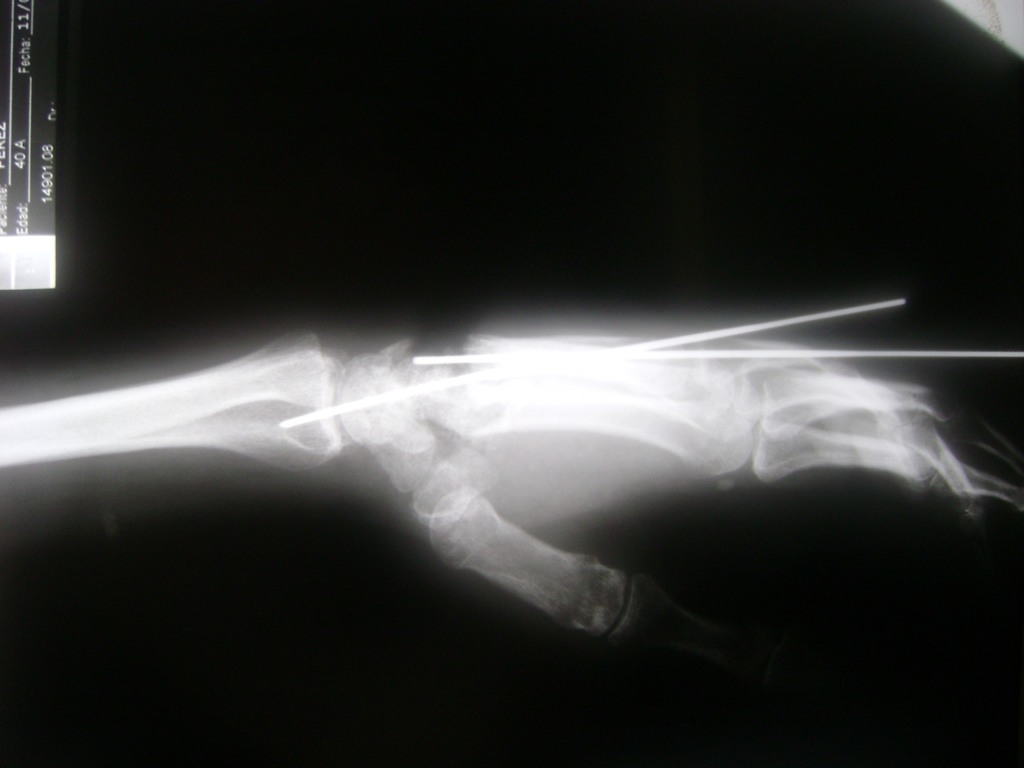

Cirugías de Hombros - Cirugías de Muñecas y Manos

Los procedimientos más comunes en cirugía de la mano son aquellos destinados a reparar traumatismos, incluyendo lesiones de tendones, nervios, vasos sanguíneos, y articulaciones; huesos fracturados; y quemaduras, cortes, y otros daños de la piel.